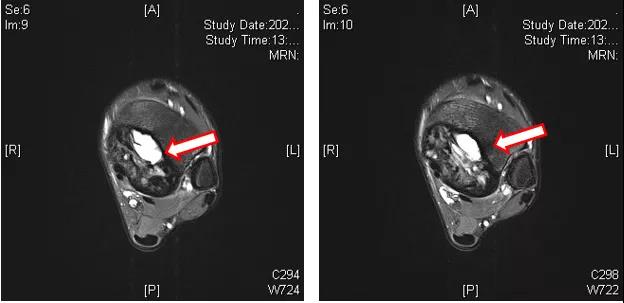

辅助检查:左踝MRI(2020-09-03):左侧胫骨内侧髁关节面下见团块状T1WI等信号、T2压脂不均匀高信号影,内见多发囊腔;病变大小约为27 mm(前后)×39 mm(左右)×45 mm(上下),边界清楚,病变后缘向后膨隆,周围软组织见条片状压脂高信号影(T2WI脂肪抑制序列病变周边高信号),环绕胫骨下端周长2/3。左侧胫骨内侧髁关节面下占位性病变,考虑骨巨细胞瘤可能性大(图1~3)。

图1:左踝MRI(2020-09-03)

图2:左踝MRI(2020-09-03)

图3:左踝MRI(2020-09-03)